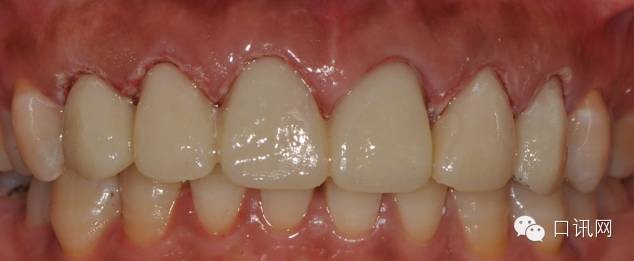

修复体完成后正面观

修复体完成口内照片